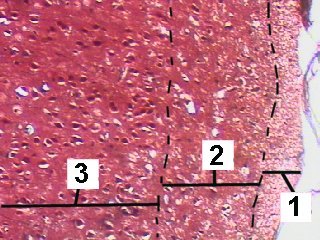

A low magnification of the cortex from the area where the cells of Retz occur.

The cortex consists of 6 weakly differentiated layers.